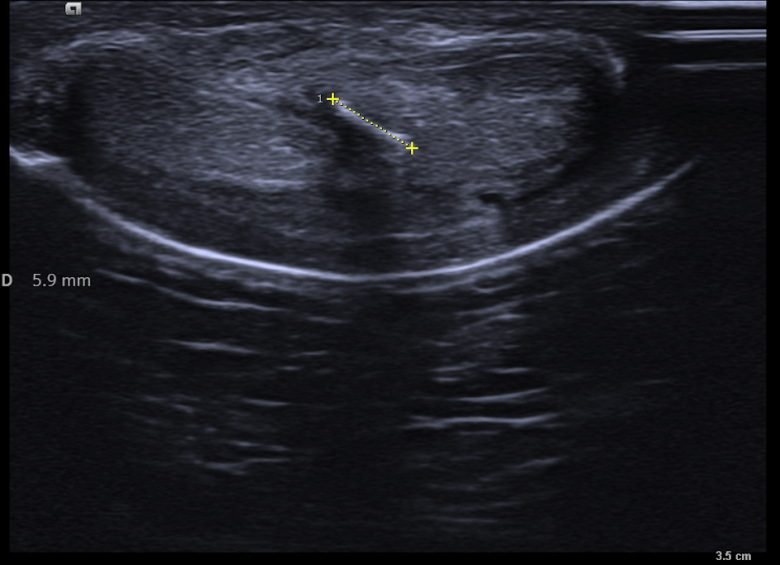

Estas tres próximas imágenes que vas a ver son tres claros ejemplos de lo que es una calcificación grosera de la túnica albugínea, mira:

En estas tres imágenes ves claramente una calcificación grosera, ligeramente curva, que afecta a la túnica albugínea del cuerpo cavernoso izquierdo en su porción interna y profunda. Mide algo menos de 7 mm y esto ya se considera una placa bastante grande. El paciente, por cierto, no cumplía con los estándares de incidencia habitual, tenía menos de 40 años.